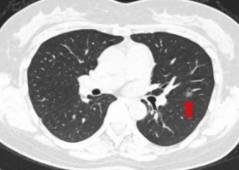

随着医疗影像设备精准度提高,分辨率较前明显提高,之前不能发现的肺补小结节可以被发现。这些结节多数是良性的。为之前肺部感染留下的印记,不必处理。但也不能除外肺肿瘤可能,所以要定期复查,观察结节变化,如结节增大,呈磨玻璃影有毛刺或胸膜牵拉现象要及早手术治疗。

如果没有临床症状,可在半年左右的时间复查一次肺CT检查,或者做增强肺CT检查,确认肺小结节的部位、大小如何?肺小结节不超过五个毫米,没有临床症状,可半年左右复查一次肺CT检查,连续三次都没有变化,再间隔一年左右复查一次,连续三年复查没有变化是为良性。请你不要过度紧张,如果没有临床症状,不发烧,不用服用任何药物。要多吃优质蛋白的食物,每天坚持到户外做有氧运动,一个半小时左右,以增强自身的免疫力和抗病体质。祝你永远健康快乐每一天!